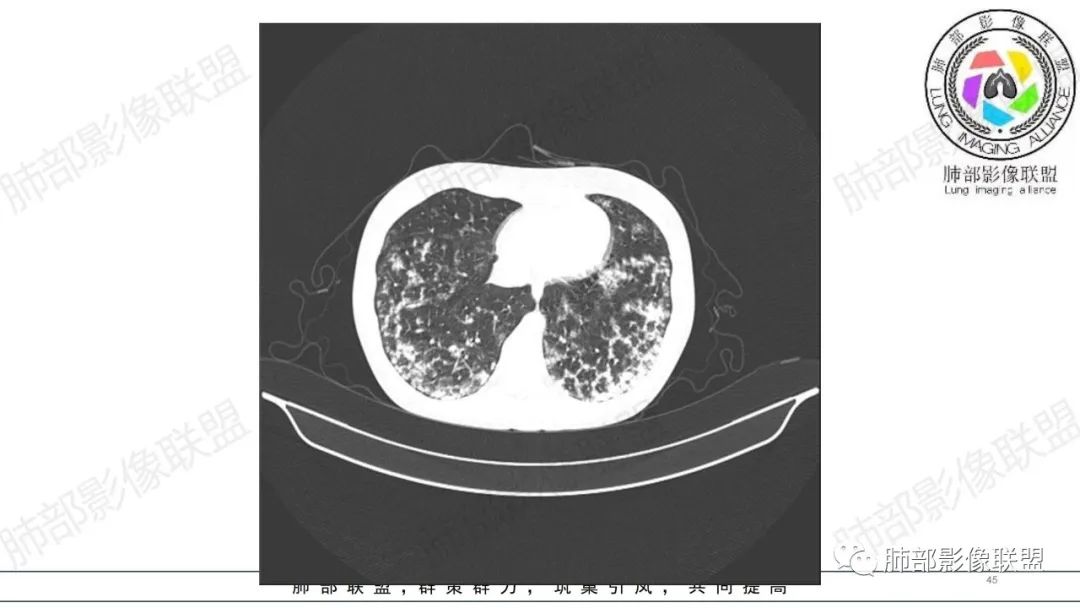

34岁女性患者,“哮喘”病史30年,近期有可疑刺激性气体吸入史;因乏力半年,咳嗽、憋气、发热4天就诊;6.1CT提示双肺广泛毛玻璃影及粟粒样结节,胸膜下闲置及血管周闲置,可见树丫征,部分小叶间隔增厚。考虑:1.过敏性肺泡炎,有可疑刺激气体接触史,胸膜下闲置,广泛毛玻璃影,地图样分布,粟粒结节边界模糊,支持过敏性肺泡炎,但糖皮激素治疗效果不佳,且动态复查血常规血红蛋白进行性降低,过敏性肺泡炎 不符合;2.肺含铁血黄素沉积症:患者30“哮喘”病史,可能为肺含铁症状,肺部CT提示双肺弥漫毛玻璃影及粟粒结节影,中下肺明显,肺底部分小叶间隔增厚,近期咳嗽、憋气、发热,血常规血红蛋白进行性下降,考虑肺含铁急性期症状,但临床无咯血症状,肺含铁不典型。综合考虑:肺含铁血黄素沉积症>过敏性肺泡炎。

年轻女性 ,急性喘息发热,肺部影像弥漫磨玻璃密度,部分细小腺泡结节,胸膜下黑线显示,短期复查,病变密度增高,下肺明显,血管周围肺组织累及较少、且逐渐成小叶间隔分布。考虑弥漫肺泡内病变,并经淋巴道转移,下肺比上肺明显,多为免疫细胞功能下肺较强。1.过敏性肺泡炎,有相关病史,三层密度特点、头尾测分布,符合。2 肺泡微石症,多有钙化,且缓慢起病,病程不太符合,放待排。3 吸入相关肺损伤,有病史,疾病演变过程也符合渗出-肉芽肿改变,建议详细询问病史。4 感染性病变,结核?病变气道分布为主,如此弥漫且没有树丫不符合。5.巨细胞病毒,可以磨玻璃 结节 改变,没有免疫缺陷病史。最后考虑吸入所致 1过敏性肺泡炎、吸入性肺损伤 鉴别肺泡微石症。

肺内气腔磨玻璃结节,肝脾肿大,治疗后间质改变,弥漫大B可能